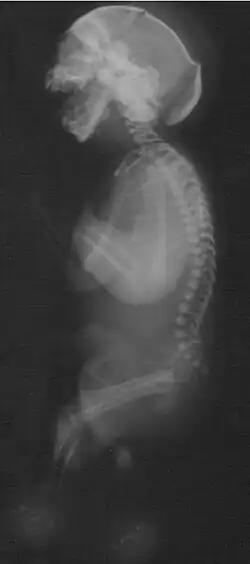

Zespół Neua-Laxovy (zespół Neua-Povysilovy, ang. Neu-Laxová syndrome, Neu’s syndrome, Neu-Povysilová syndrome, NLS) – letalny zespół wewnątrzmacicznego zahamowania wzrostu i mnogich malformacji.

Do obrazu klinicznego tego rzadkiego zespołu należy długa lista wad wrodzonych, w tym:

- wady ośrodkowego układu nerwowego:

- lissencefalia

- agenezja ciała modzelowatego

- mikrogyria

- mikrocefalia

- nasilony obrzęk tkanki podskórnej

- rybia łuska (ichthyosis)

- atrofia mięśni

- nieprawidłowo ułożone palce

- stałe przykurcze stawów (artrogrypoza)

- wady nerek

- wady serca

- wydatna pięta

- syndaktylia palców stóp

- hipoplastyczne narządy płciowe zewnętrzne

- hiperteloryzm oczny

- brak powiek

- skrócenie szyi.